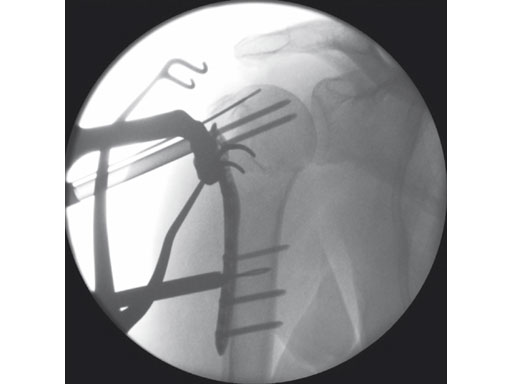

A 76-year-old woman suffered a low-energy fall at home.

Fig 3 Preliminary fixation and percutaneous reduction with bone elevator.